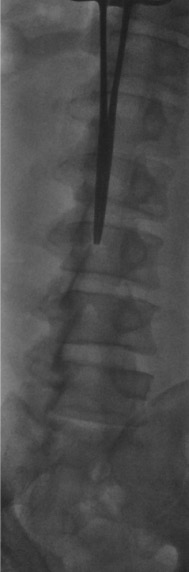

Fluoroscopic Views

When bedside US-guided or blind LP fails, fluoroscopy (prone or lateral decubitus) provides definitive guidance. The PA view confirms midline needle position; the prone oblique view opens the interspace and aligns the X-ray beam parallel to the disc for optimal interlaminar access.

- Position patient prone with pillow under abdomen; confirm with fluoroscopy that lumbar lordosis is reduced

- Fluoroscopic survey: identify target interspace (L2–L3 or L3–L4), confirm midline, assess interspace width

- Advance spinal needle under fluoroscopic guidance: midline approach for straightforward cases; oblique or paramedian approach for significant degenerative disease or prior fusion